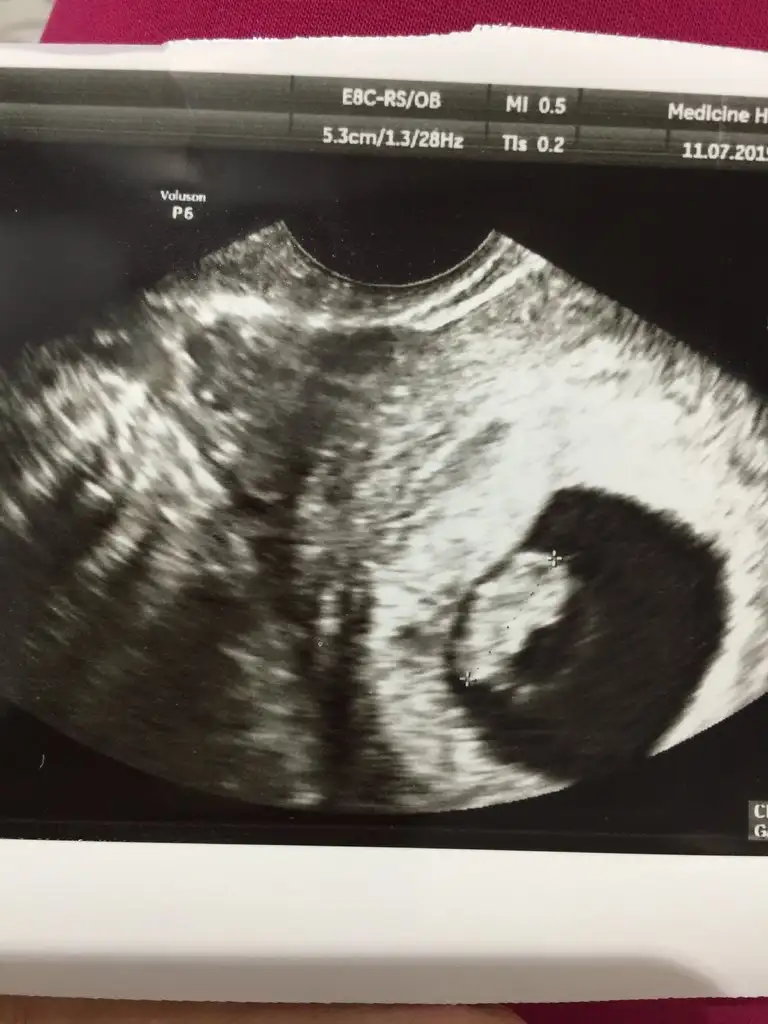

bugün doktordaydım dünkü kanamayla alakalı vajinal usg bakıldı..

7+5

• C7096772-32B0-4F3E-90FE-19C8222B4947.webp

34,3 KB · Görüntüleme: 317